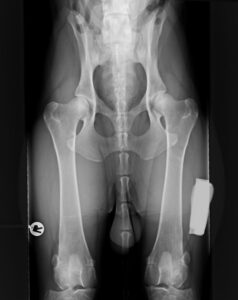

Koirien viralliset PEVISA-kuvaukset ti 3.3.2026

Ei klinikkamaksua ko. päivänä kuvauksista. Varaa aika: puh. 0600 390 301 (puhelun hinta 0,25 €/puhelu ja 0,26 €/min+pvm, jonotus on maksuton)